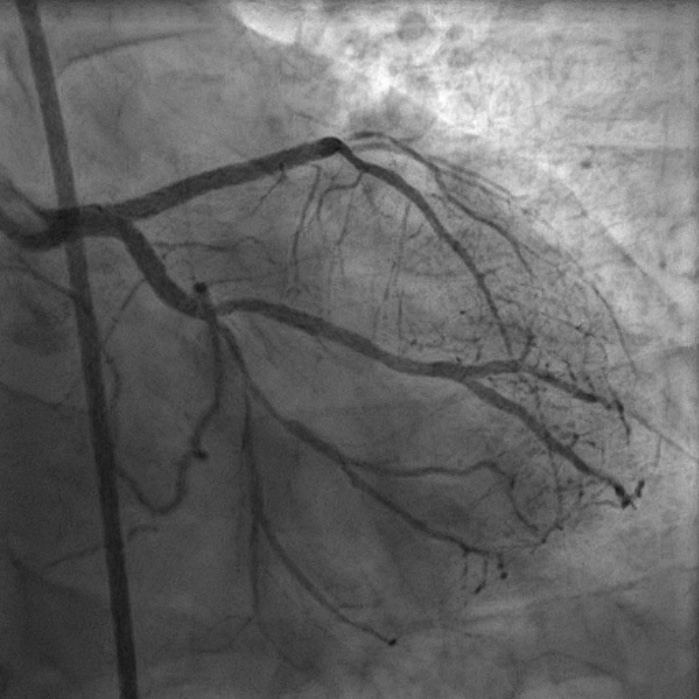

8F JL coronary guide catheter was taken from the right femoral artery and a TIG diagnostic catheter was taken from right radial artery and bilateral angiograms were taken. A floppy guide wire was placed in Lcx and ostial Lcx lesion was predicated with a 2*12 mm non compliant balloon. An IVUS catheter was placed over Lcx wire and under IVUS guidance a Gaia 3 coronary wire (Asahi, Japan) over a micro catheter was used to probe the ambiguous osmium of LAD (T1). Using contralateral injection in RCA, the Gaia 3 wire was seen extending into the false lumen in distal LAD. A Conquest Pro 12 (Asahi, Japan) was then taken over a micro catheter using a parallel wire strategy and successfully negotiated in distal true lumen of LAD (T2). After pre dilatation of LAD, Conquest Pro wire was exchanged for a floppy guide wire over a micro-catheter. IVUS run was then taken from LAD to LM and LCx to LM for vessel sizing. In view of the discrepancy in size of LAD/LCx and LM, 2 coronary stents were placed in a V technique from LM to LAD and LM to LCx and deployed. The stents were then post dilated and final kissing balloon inflation was done and the results were optimised by IVUS. Final cine showed well expanded LM LAD/LCx stents with TIMI 3 flow (T3).

Case Summary